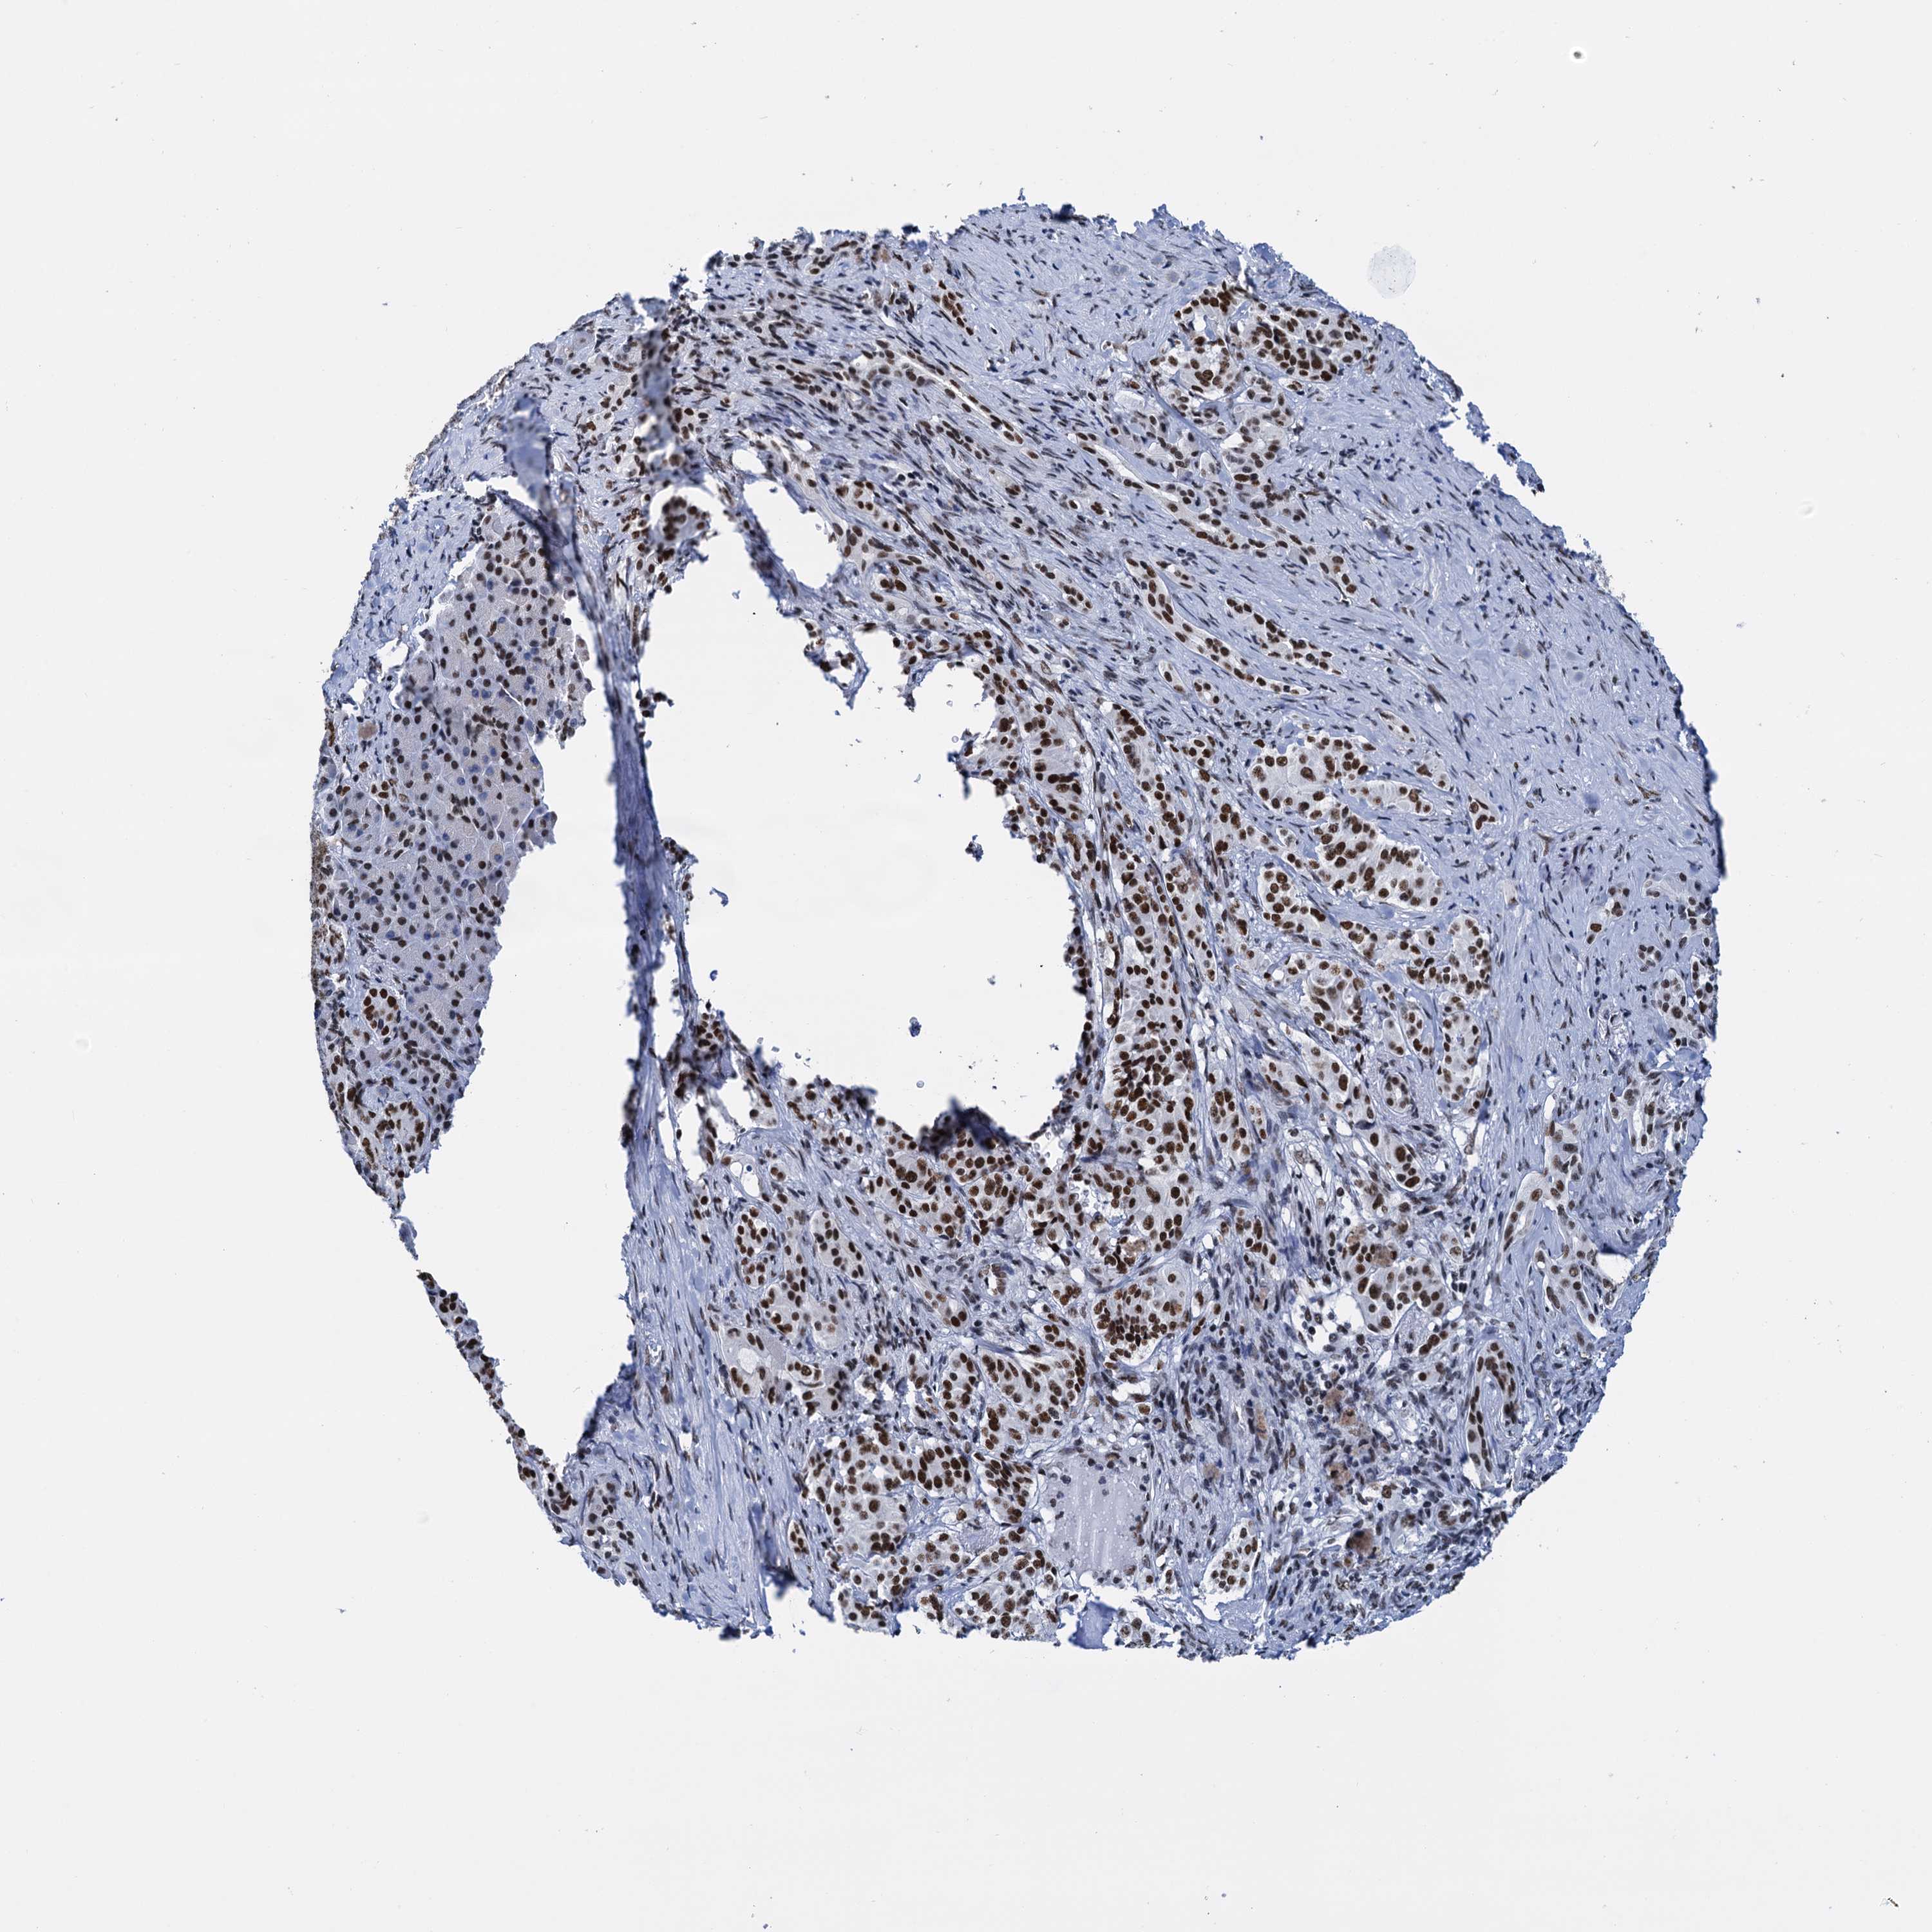

PANCREATIC CANCER - Protein expressioni

A mouse-over function shows sample information and annotation data. Click on an image to view it in a full screen mode. Samples can be filtered based on level of antibody staining by selecting one or several of the following categories: high, medium, low and not detected. The assay and annotation is described here.

Note that samples used for immunohistochemistry by the Human Protein Atlas do not correspond to samples in the TCGA dataset.

Antibody stainingi

Antibody staining in the annotated cell types in the current human tissue is reported as not detected, low, medium, or high, based on conventional immunohistochemistry profiling in selected tissues. This score is based on the combination of the staining intensity and fraction of stained cells.

Each image is clickable and will lead to virtual microscopy that enables deeper exploration of all samples and also displays staining intensity scores, fraction scores and subcellular localization as well as patient and tissue information for each sample.

Antibody HPA040256

Antibody HPA040381

Staining

High

Medium

Low

Not detected

Intensity

Strong

Moderate

Weak

Negative

Quantity

>75%

75%-25%

<25%

None

Location

Nuclear

Cytoplasmic/membranous

Cytoplasmic/membranous,nuclear

Adenocarcinoma, NOS